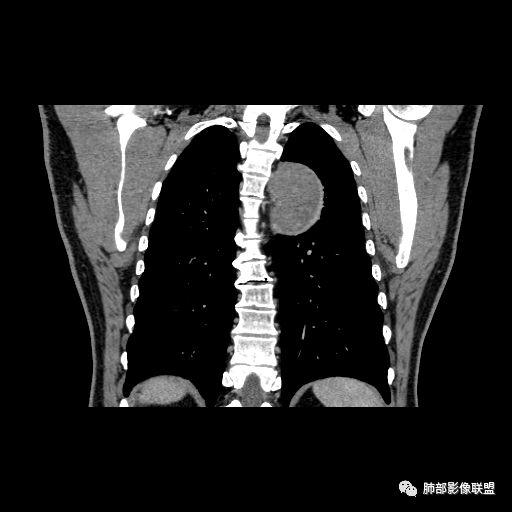

红日东升:左侧胸椎旁肿块,边缘清晰光整,冠状位见D字征,未见支气管进入,肺组织受压表现,定位肺外。轻度强化,密度稍不均匀,临近肋骨变细,未见肺动脉供血,考虑良性肿瘤,神经源性可能。右肺下叶病灶,轻度强化,血管显影,边缘平直、凹陷,考虑炎性病变。

张立:左侧胸椎旁肿块,边缘清晰光整,冠状位见D字征,未见支气管进入,肺组织受压表现,定位肺外。轻度强化,密度稍不均匀,,未见肺动脉供血,神经源性肿瘤,节细胞神经瘤可能。右肺下叶病灶,轻度强化,血管显影,边缘平直、凹陷,TB可能。

长沟流月去无声:中年男性,慢咳起病,左后纵隔可见一大占位,D字征,胸膜掀起,有胸膜尾征,附近肺组织受挤压,血管纹理纠集,瘤肺界面清晰,较均匀轻-中度强化,瘤肺表面可见线样不张之强化影,供血血管来源不易确定,冠状位似乎见一纵隔血管出入,综合考虑神经源性肿瘤:神经纤维瘤,神经鞘瘤?右下外斑片密度影,估计炎性,但本次手术应该未处理。

张秀兰:定位:肺外来源没问题表现,紧贴胸壁,胸膜尾征,点状钙化,密度均 匀,轻度强化考虑:神经源性肿瘤,鞘瘤首选,节细胞瘤待排鉴别:1单发胸膜间皮瘤,间皮瘤也有强化,程度比这个略甚,少见2孤立性纤维瘤,血供丰富,小的瘤体也有比较明显的强化,瘤体越大滋养血管越丰富,强化越甚。

ZK金:定位:左肺下叶后综合脊柱旁肺外肿块,胸膜尾征,D字征,瘤肺交界面清晰,肺组织受压。影像表现:边界清晰,密度均匀,上下经线略横经。首先考虑神经源性肿瘤,神经节细胞瘤首选,鞘瘤和孤立性纤维瘤鉴别诊断。右肺下叶考虑炎症。

M-Imaging :冠状位,还是靠近纵隔来源的

1.左上胸内脊柱旁半圆形肿块,质地坚实,密度比较均匀。

2.病灶周边见胸膜掀起,应当考虑胸壁或是纵隔来源,肺内病变不会如此。

3.降主动脉这一相对固定结构向前方推移,提示病灶相对坚实且有牢固附着点,不支持来自柔软的肺组织。

就如同在腹部,能将肾脏推移的包块,应该来自腹膜后。

4.可疑肋间动脉病供血,提示肿块来自后纵隔的可能性。

5.相邻椎间孔未见扩大,也未见块影延入椎管,易起自于神经根的鞘瘤似乎找不到相关支持点。

6.未提供矢状位骨窗图像,如在肋骨内下缘观察到压迹有助于肋间神经的鞘瘤的判断,这是因为二者之间密切的毗邻关系。

7.静脉期轻度强化,注意不是环形强化,亦未显示明确的“AB区”,神经鞘瘤与副节瘤亦未找到支持点。

综上,病灶定位胸壁或后纵隔,就发病率而言,神经源性可能性较大。